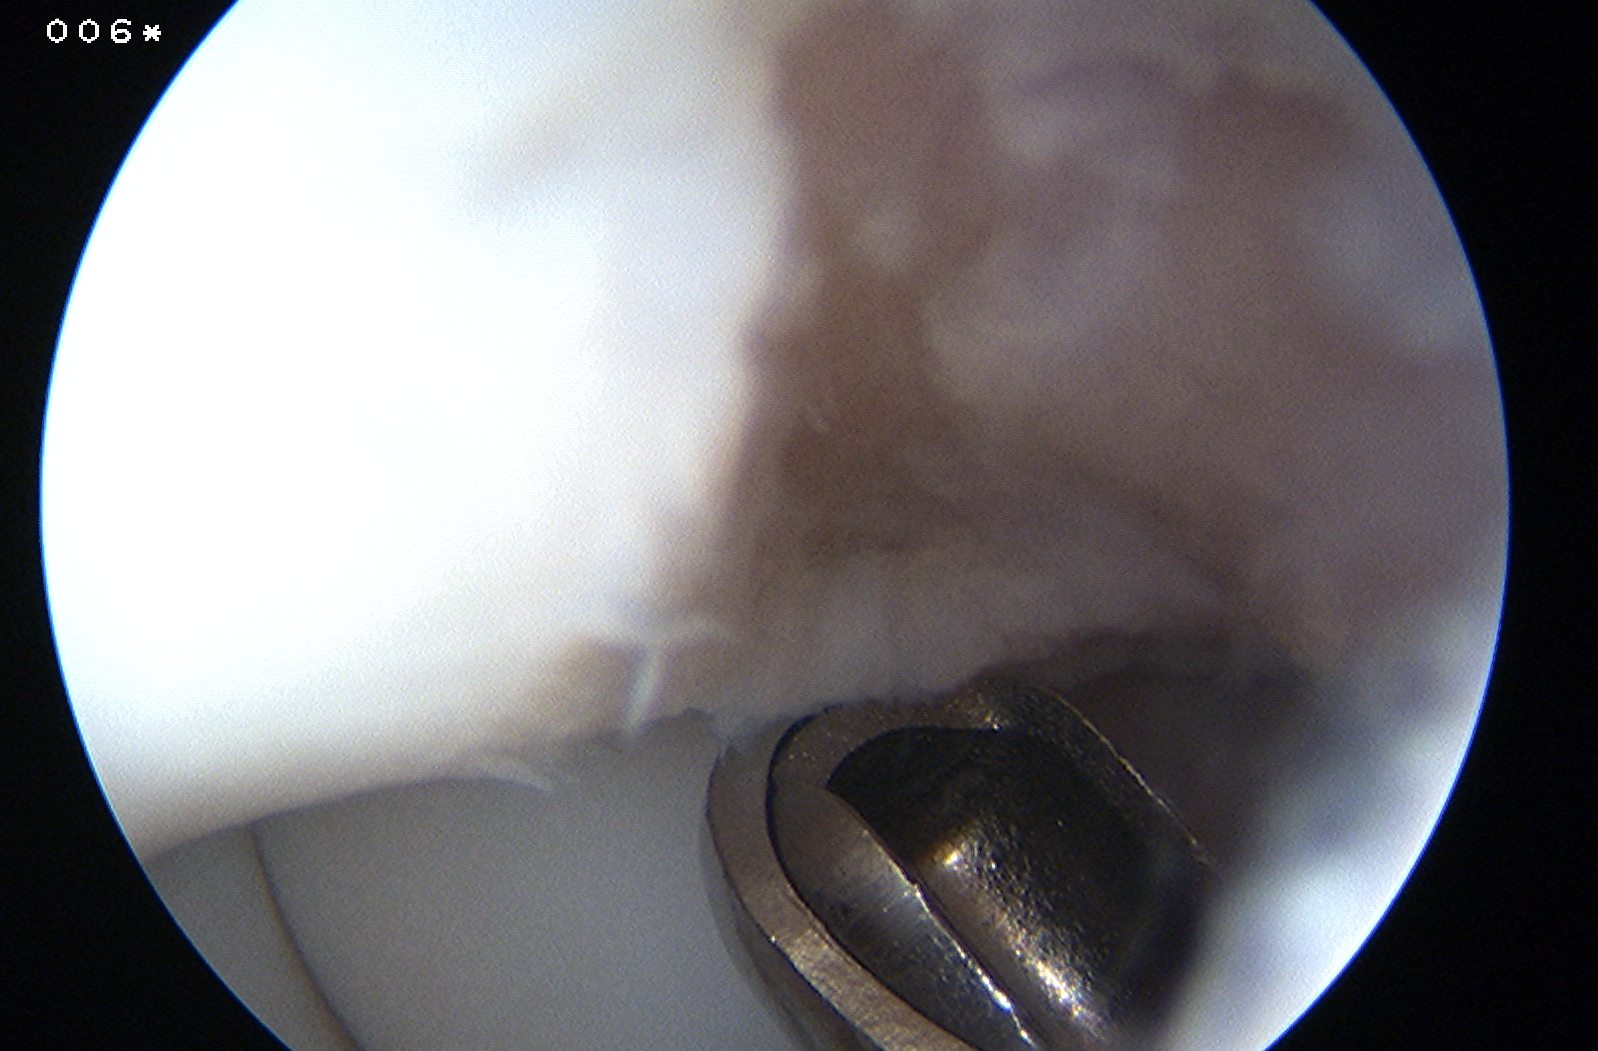

Drill in situ

Indications

Stable lesion

Failed nonoperative treatment

Capitellar OCD viewed via anterior portals, being drilled in retrograde fashion using ACL jig

Arthroscopic technique

1. Anterograde

2. Retrograde using ACL jig